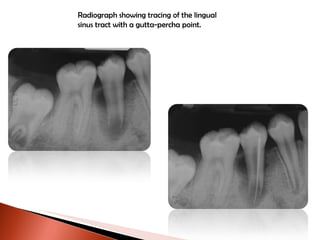

Radiograph showing tracing of the lingual sinus tract with a gutta-percha point.